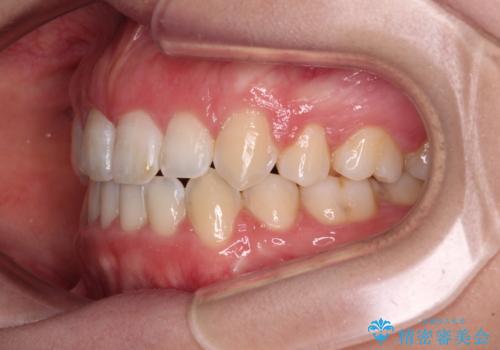

- 口元の突出感と口の閉じにくさ、前歯のデコボコを気にして来院された患者様です。

上下左右第一小臼歯4本を抜歯し、ワイヤー装置にて口元を引っ込めるよう矯正治療を行うこととしました。

骨格的に下顎骨が前方位にあるため、口元の突出感改善には限界があると思われましたが、唇の閉じにくさが改善するほど引っ込めることができました。